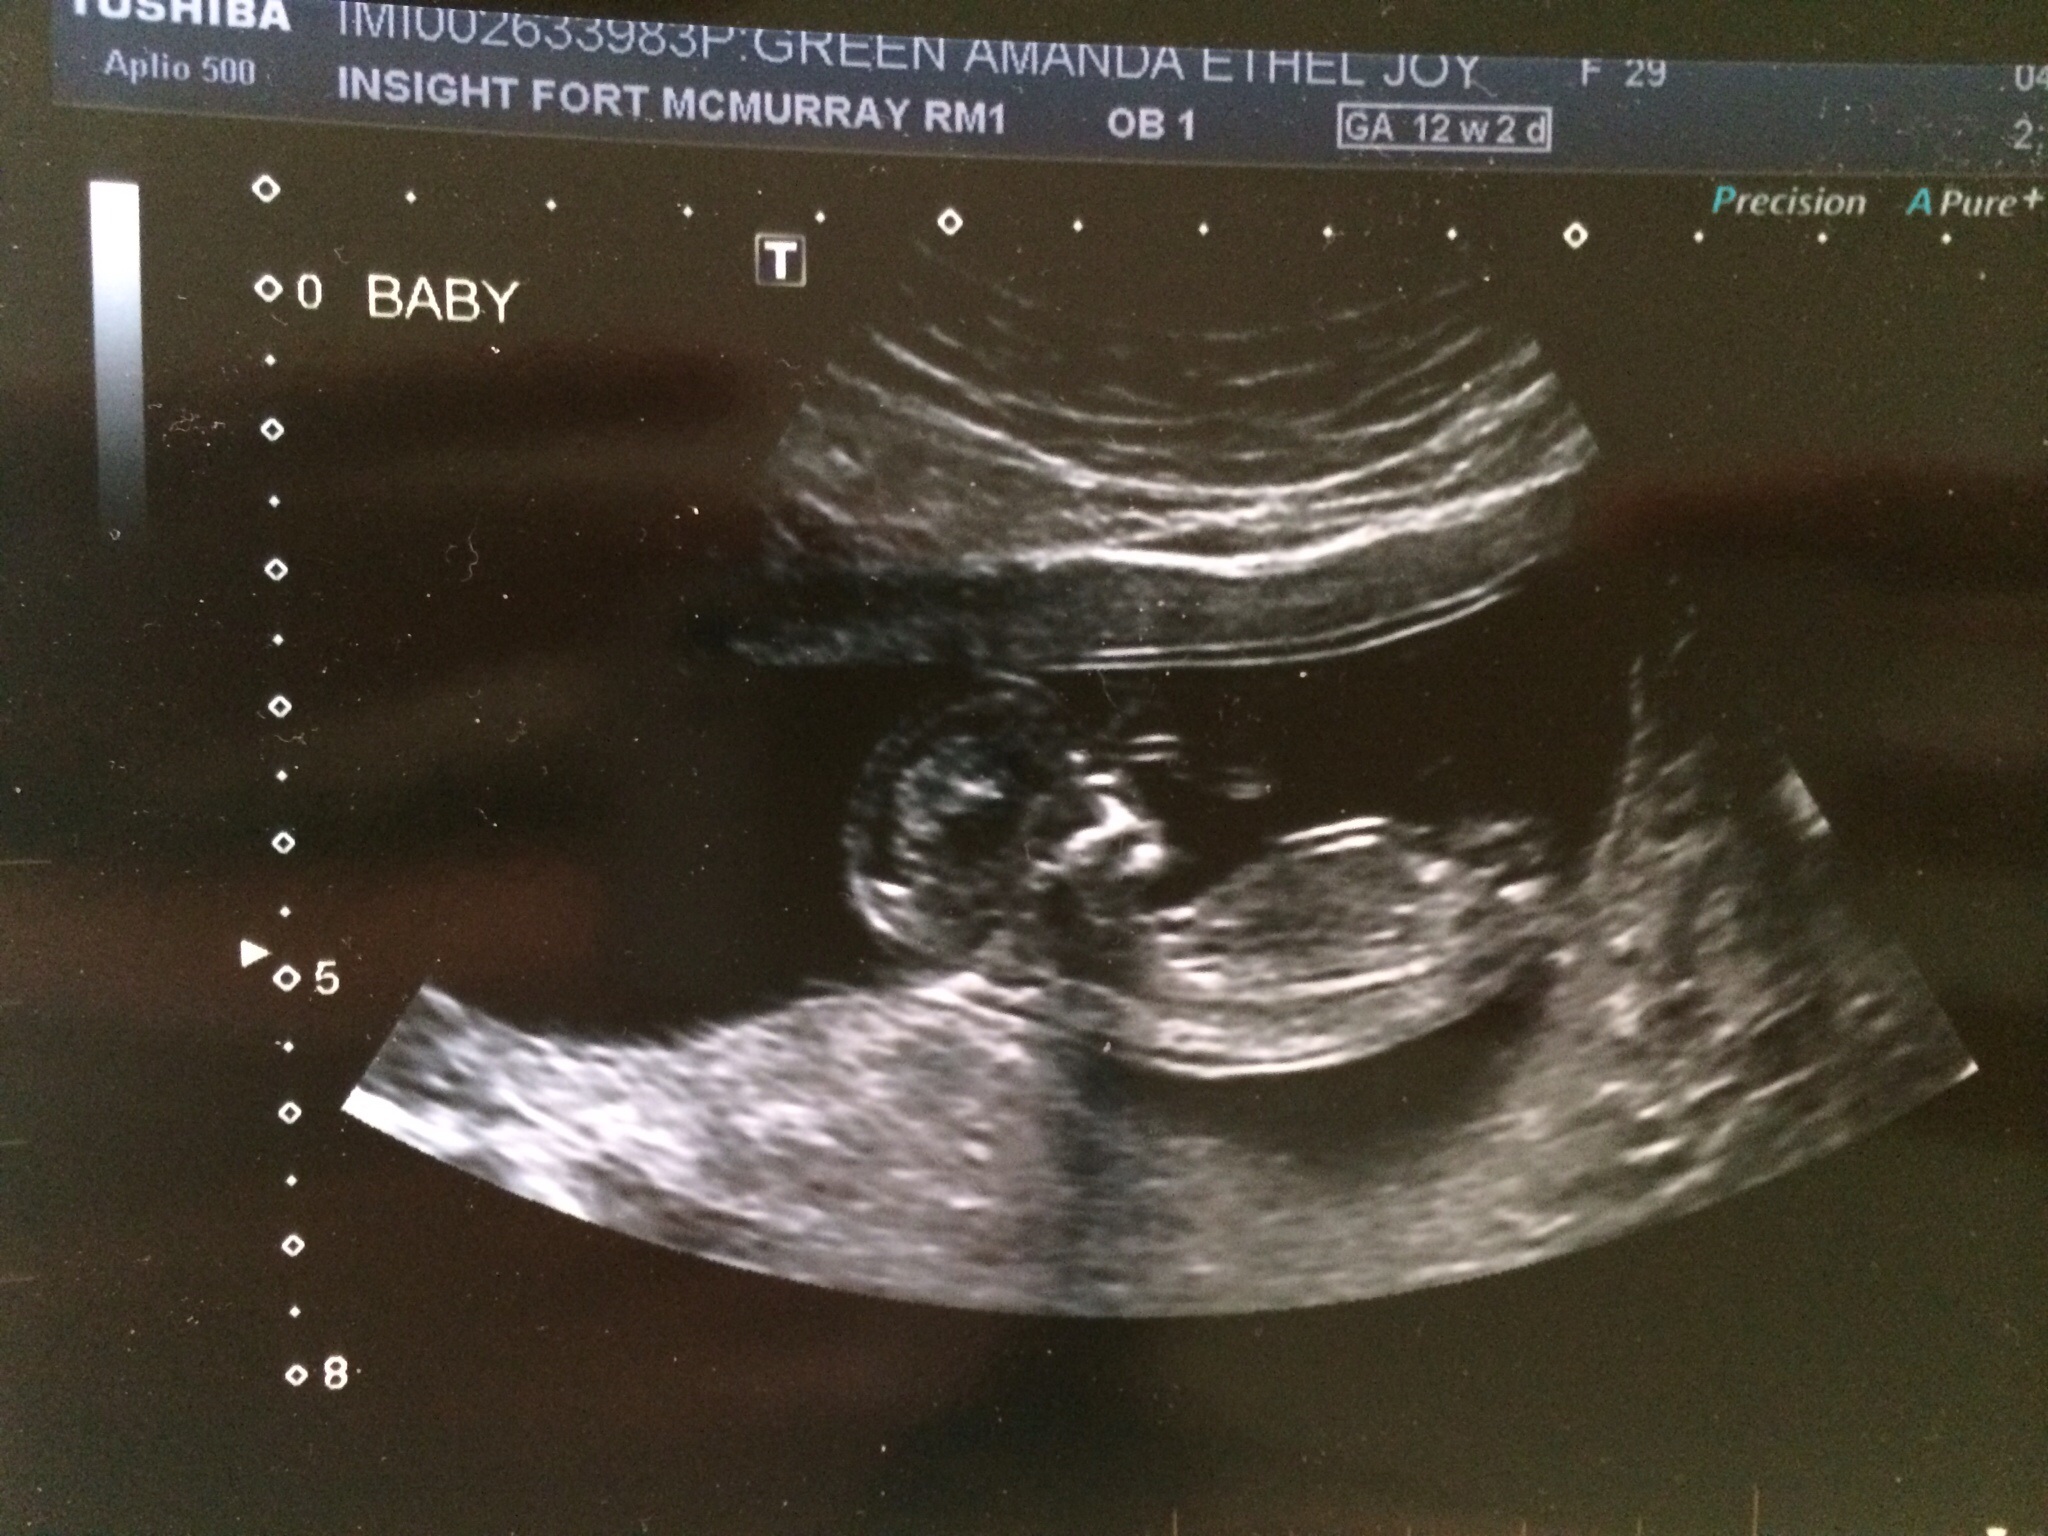

Had my ultrasound today... She couldn't find the blood clot! But she did find a healthy active baby with a heart beat of 166bpm. The GA is 12w5d instead of 12w2d... Very happy!

@emily.jeanne glad baby is ok! How did your U/S look? We had our NT testing yesterday and the ultrasound tech said she couldn't find the SCH. But when I look at my picture it looks like a SCH underneath baby.... I have to wait for a week to see the OBGYN. what did your ladies look like and what do you think ?

@amandaejgreen I think that is way too close to baby to be a SCH, I think it's just fluid behind it's back. You can see mine is the thin black line under the baby's rump almost at the edge of the picture.

Oh yes, I see it! Has it gotten any smaller ? I'm trying not to be nervous but the NT testing I think is stressful... Can't wait to get the results on Monday.